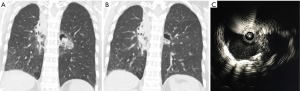

There are many novel ways EBUS is being used in the diagnosis and treatment of intrathoracic disease. We and others have combined RP- EBUS and CP-EBUS with cone beam CT to facilitate biopsy of difficult to locate central and peripheral pulmonary nodules (Figures 3,4) (65). A randomized controlled trial is currently underway to determine if this technique improves diagnostic yield (NCT02978170). For thyroid malignancy EBUS has been used for diagnosis and staging in patients with lesions not amenable to percutaneous biopsy (66). It has also been used to evaluate for airway invasion in the setting of esophageal and thyroid cancer and has higher sensitivity and specificity than magnetic resonance imaging or CT (67). EBUS may also play a role in diagnosis and treatment of cardiac disease and has been used to facilitate percardiocentesis for posterior loculated pericardial effusions (68). Among 32 patients with CT proven pulmonary embolism, EBUS was utilized in a pilot study to confirm a diagnosis of central pulmonary embolism in every patient with an average procedure time of only five minutes (69). EBUS has been utilized for bronchogenic cyst drainage in patients who were not good surgical candidates and for treatment of cyst recurrence after partial resection (70,71).